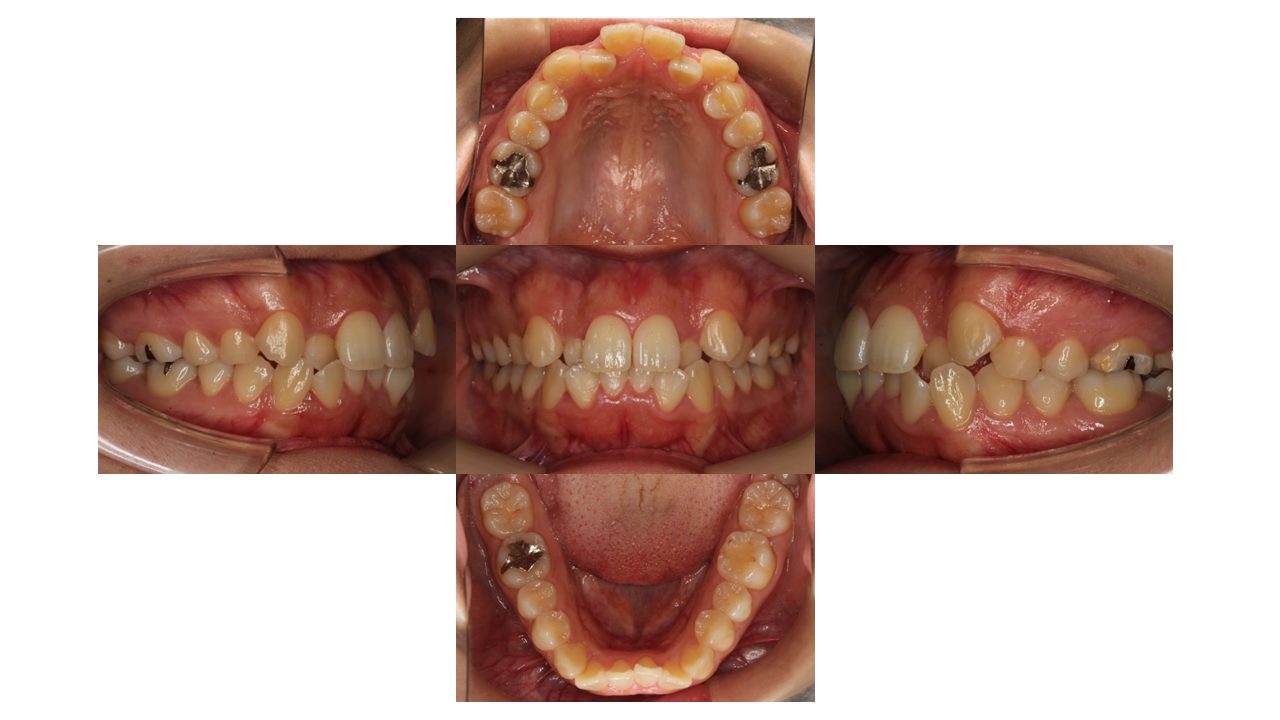

初診時の口腔内の状態です。

前歯の凸凹・八重歯にお悩みでご来院されました。